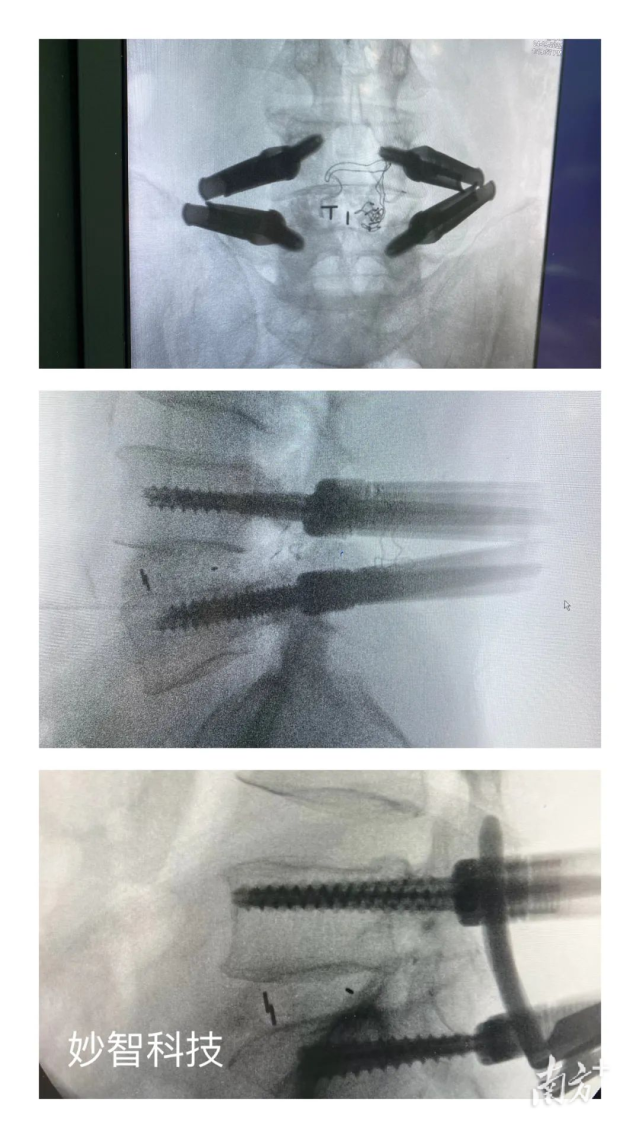

妙智科技研發(fā)的骨科機(jī)器人在臨床中試驗(yàn)

由於新型醫(yī)療器械壹般研究周期較長,目前,妙智科技研發(fā)的骨科機(jī)器人仍在臨床試驗(yàn)階段。截至2022年底,妙智科技已經(jīng)完成了近50例臨床病例,預(yù)計(jì)今年計(jì)劃將完成取證並開始售賣。